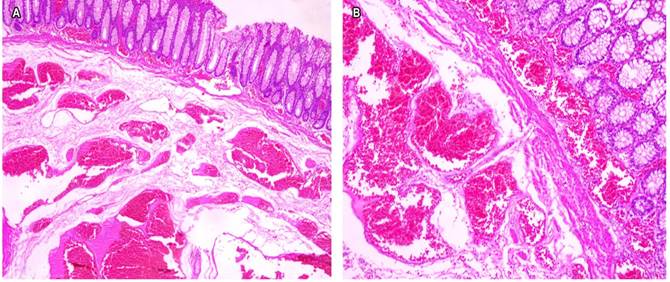

En el servicio de patología se recibió un segmento de colon que mide 17 x 8 x 3 cm, de color violáceo. Al corte de identificaron múltiples vasos engrosados, de contenido hemorrágico, que ocupan y ocluyen la luz en un 50%, la lesión se encuentra a 1,5 cm de los márgenes de resección. En el examen microscópico se observó mucosa colónica con una lesión vascular múltiple, que compromete todo el espesor de la pared y está constituida por una proliferación de vasos dilatados, de mediano y gran calibre, tapizados por células endoteliales sin atipia y en su interior algunos se encontraron trombosados, con focos de hiperplasia papilar endotelial y algunas áreas con contenido eosinofílico en su interior (Figuras 2 y 3).

Figura 2 Representación de la lesión en la que se observan vasos sanguíneos de diferentes tamaños en la submucosa. En la parte superior se observa mucosa rectal sana. A. Hematoxilina-eosina (HE) 4x. B. HE 10x.